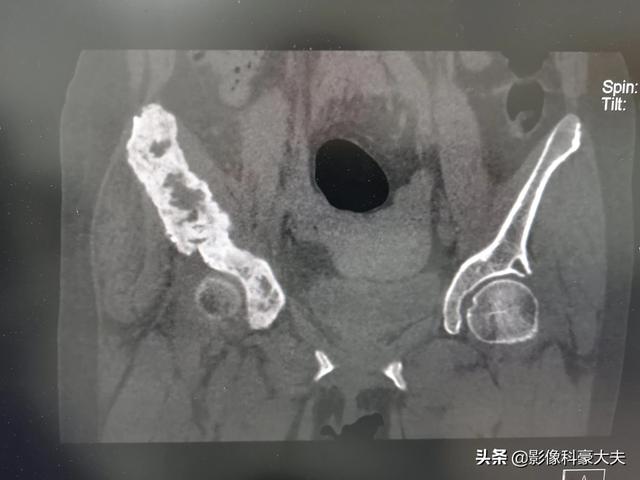

Ce patient souffrait de douleurs à la hanche et d'une suspicion de nécrose de la tête fémorale, ce qui a conduit à la détection de métastases osseuses au scanner du bassin et les examens complémentaires ont révélé un cancer du poumon à un stade avancé.

Le cancer peut métastaser dans les os de différentes parties du corps, les plus courantes étant généralement les os du milieu de la colonne vertébrale (c'est-à-dire les vertèbres thoraciques et lombaires), le bassin, les côtes et l'omoplate. La douleur se manifeste dans la partie de l'os où se trouvent les métastases. Par exemple, les métastases au niveau de la colonne lombaire provoquent des douleurs lombaires et les métastases au niveau de l'omoplate provoquent des douleurs à l'épaule. En outre, certains patients consultent un médecin parce qu'ils ressentent une douleur dans la zone métastatique. J'ai une impression profonde d'un patient, âgé d'une quarantaine d'années, qui avait des douleurs à l'épaule, pensait qu'il s'agissait d'une épaule gelée, a frotté l'huile médicinale sans effet, et la douleur est devenue de plus en plus grave, puis est allé à l'hôpital pour voir le médecin lorsque la douleur était trop insupportable, et le résultat de l'examen était la métastase de l'omoplate du cancer du poumon et l'omoplate avait été détruite par la tumeur métastatique. Les informations sont les suivantes : cancer du poumon (tête coupée) métastase de l'omoplate gauche, l'os a été détruit par la tumeur en un morceau (cercle).